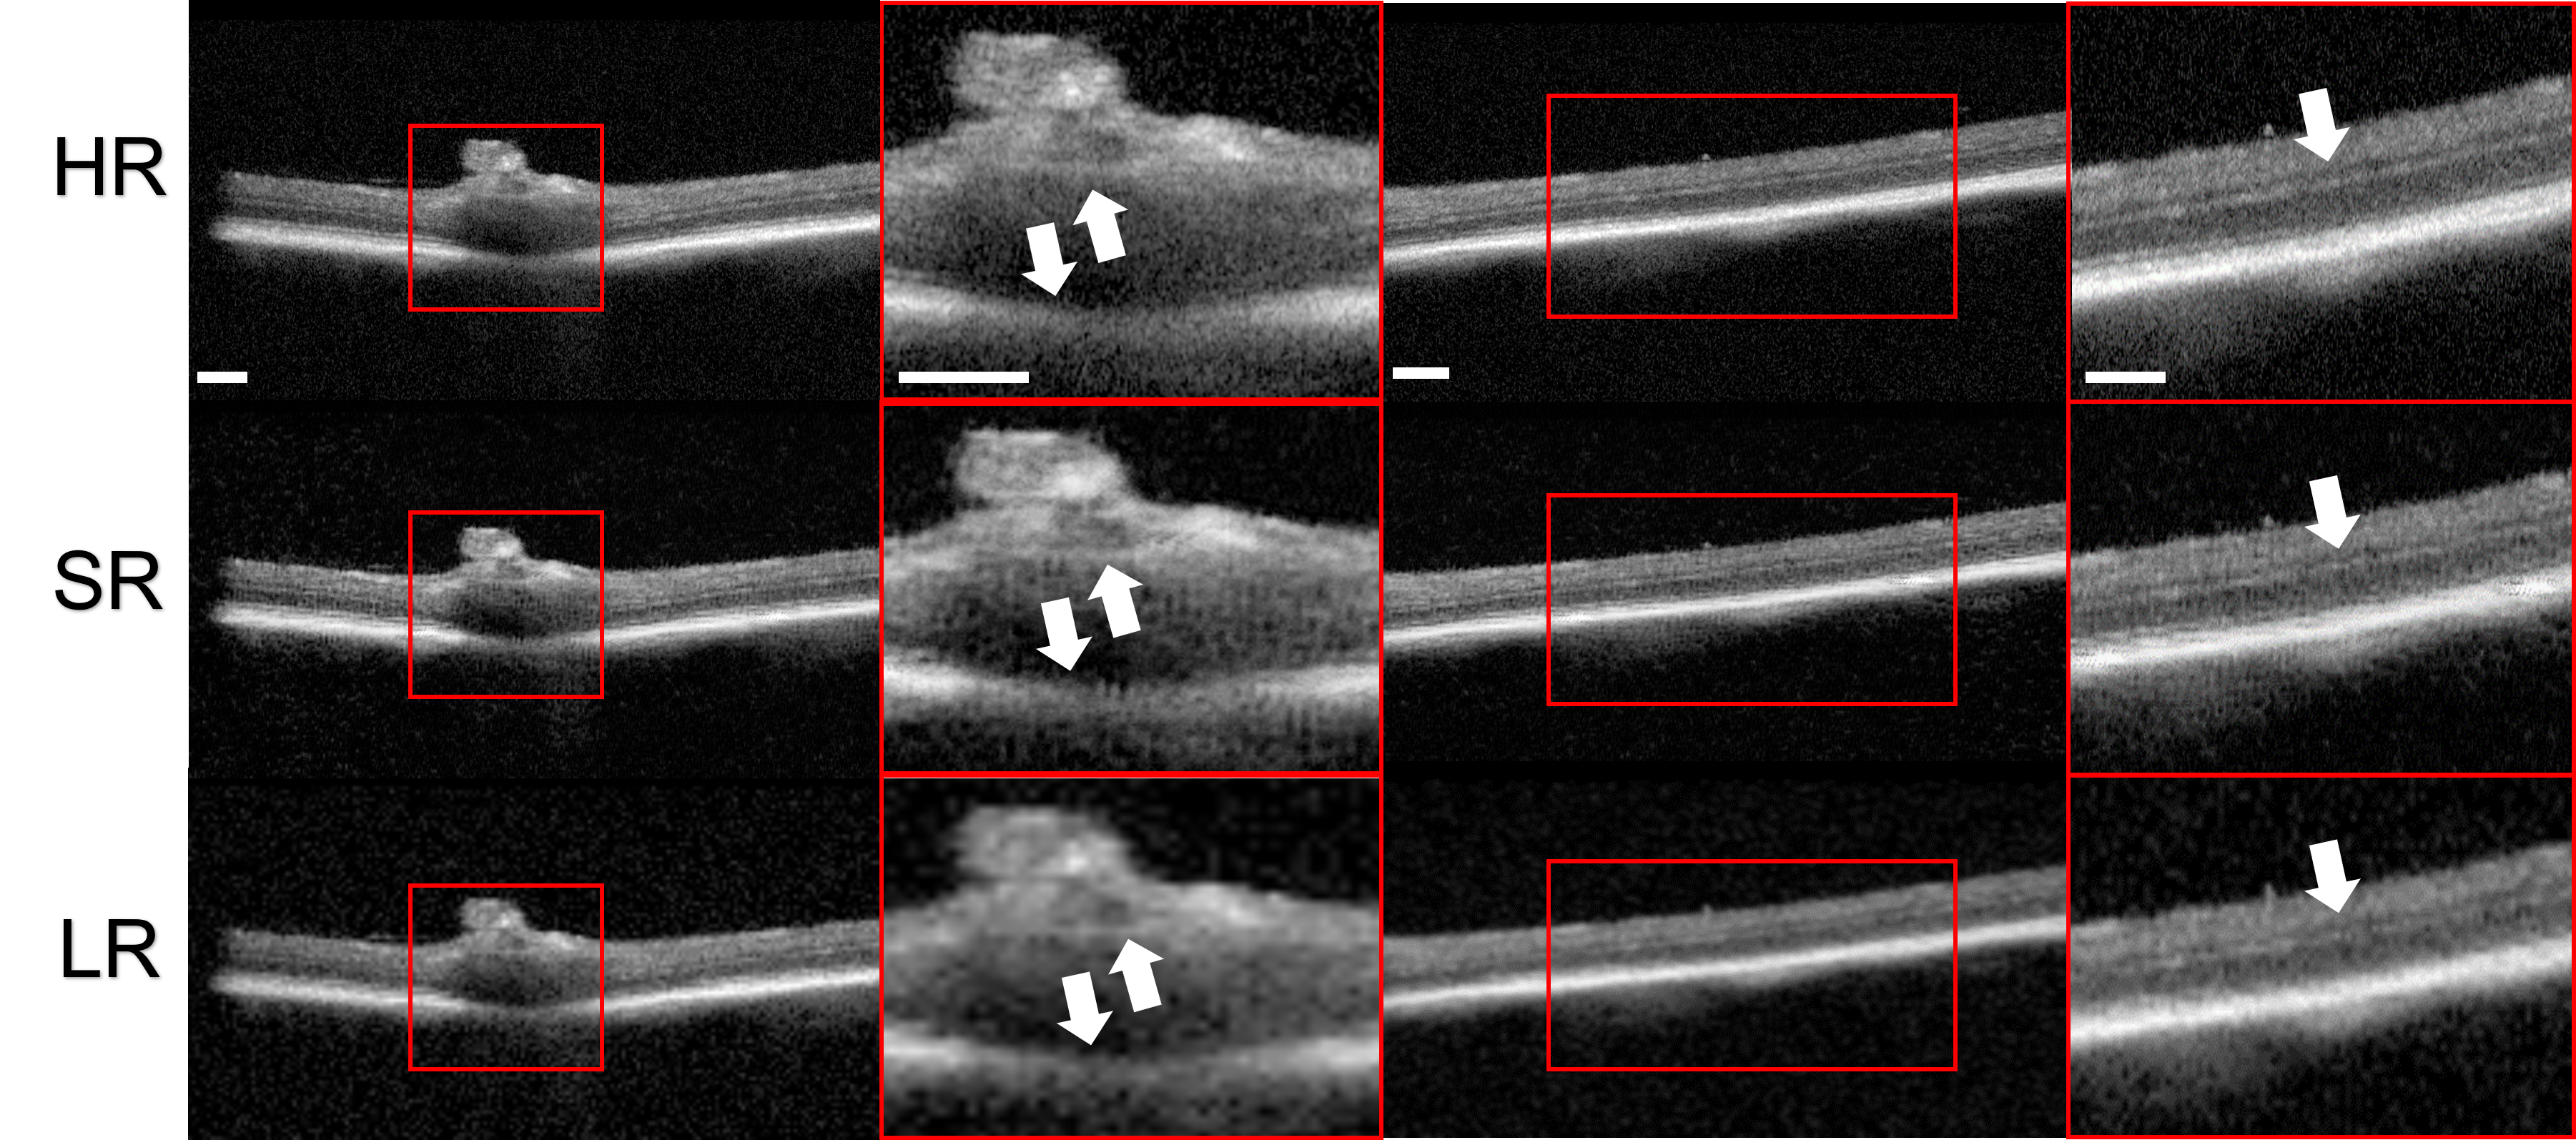

In Fig 5, we demonstrate a case of super-resolving an LR OCT image of suspicious accumulation of macrophages. Macrophages play a critical role in both the development and rupture of atherosclerotic plaques [34], which are thus important for the diagnosis of CAD. OCT has been demonstrated to be a viable technique for visualizing the accumulation of macrophages in the human coronary artery. Macrophages appear as ’bright spots’ in OCT images [35], which are high-frequency information due to their sharp contrast with neighboring tissues. As shown in Fig 5, previous DL algorithms generate SR images with blurred macrophages, which will deteriorate the clinical diagnosis procedures. In contrast, our frequency-aware framework generates SR OCT images with clear macrophages. Thus, our frequency-aware model is capable of providing SR OCT images for human coronary samples with clinical meaningness.

3.9 Application to super-resolve posterior segments of rat eye

We also conduct experiments to imaging posterior segments from animal model. A pigmented Long Evans rat from Charles River is used for OCT imaging. Retinal imaging requires a different optical design from benchtop OCT was used in coronary imaging and corneal imaging. The OCT images were acquired using Heidelberg Spectralis system. We retrained the frequency-aware framework using of the images and used the rest of the images for testing. The SR OCT images of rat eyes generated by our frequency-aware framework are shown in Fig 7. In the first panel, the SR OCT image delineates the boundary around optical disc; and in the second panel, the SR OCT image better resolves the layer boundary within retinal regions (for example, inner nuclear layers). This experiment shows that our proposed frequency-aware framework, with adequate retraining, has the potential to be generalizable to OCT retinal images obtained from different OCT systems.

Another contribution lies in generalizability. Our preliminary study indicates great potential to be applied to multiple tissue types. We perform qualitative experiments on additional fish eye and rat eye dataset. Without retraining, our frequency-aware framework resolves anterior segments of fish eye, including corneal stroma, iris region, and downman’s layer, acquired from the same OCT system. With adequate retraining, our frequency-aware framework is capable of resolving LR OCT images acquired from different systems. From the qualitative analysis of a rat eye dataset acquired from a different OCT system, we resolve the boundary around the optical disc and within retinal regions, with adequate retraining.